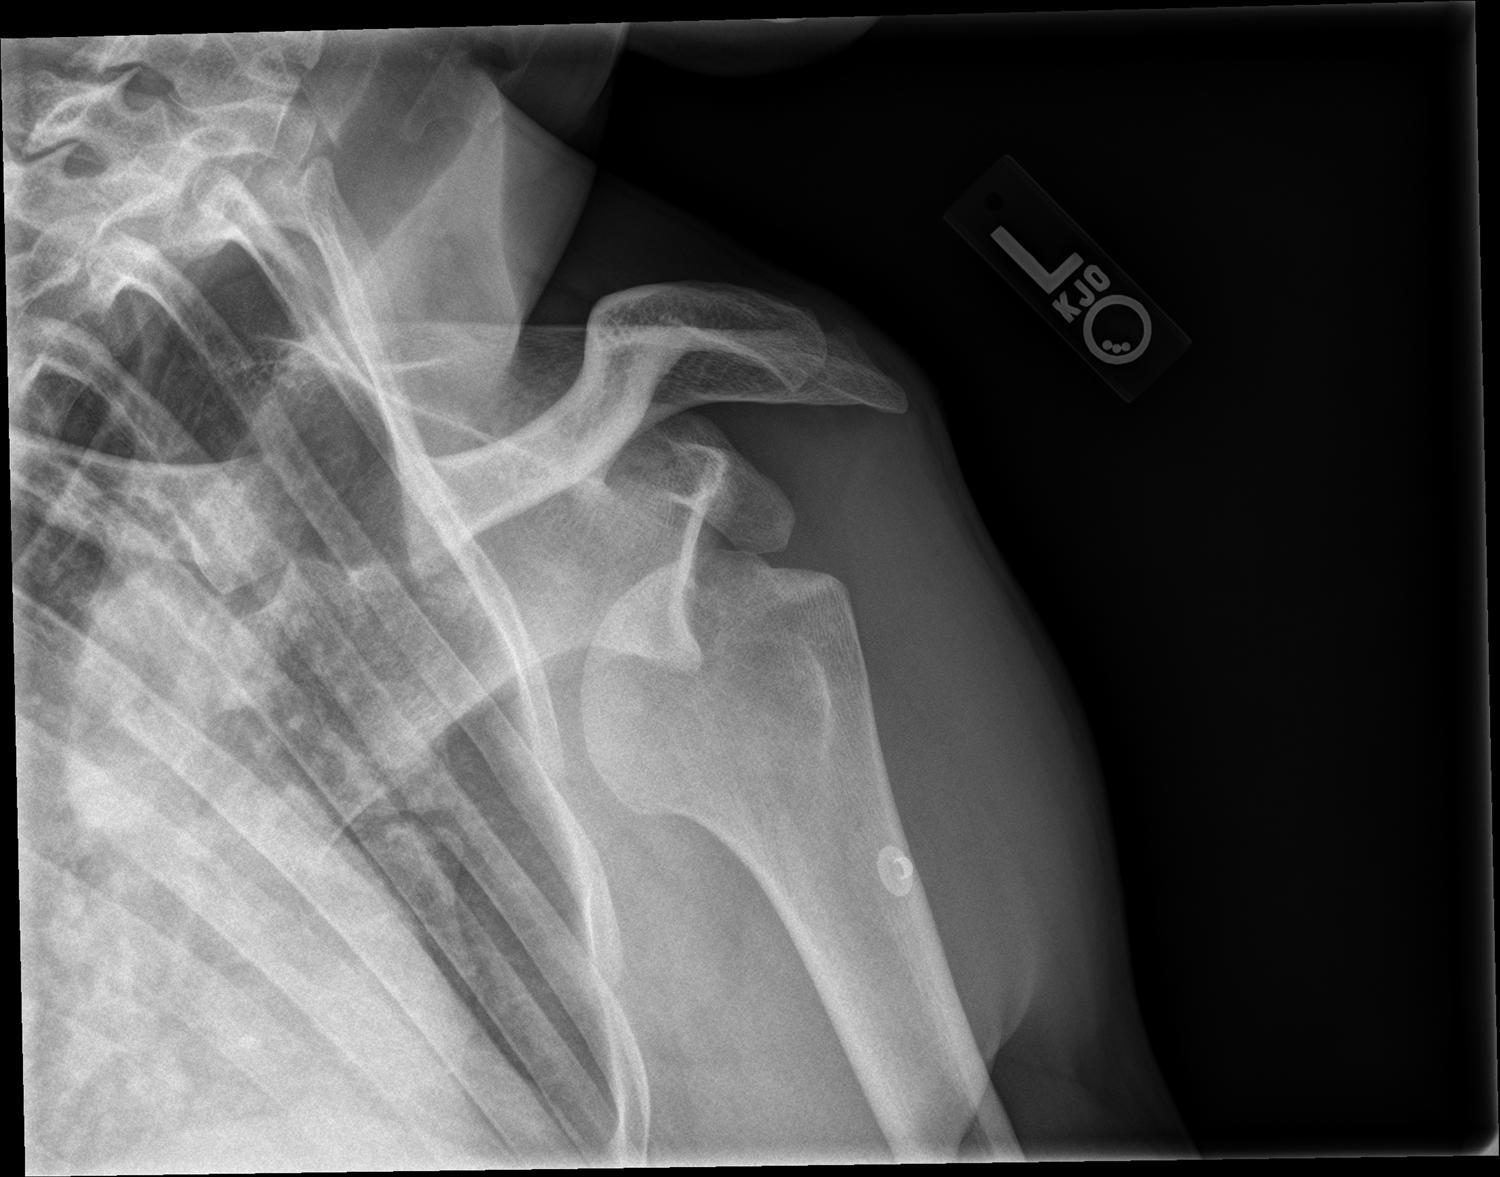

Shoulder Fracture with Dislocation Medical Case Study Sydney Shoulder Dislocation After Rotator Cuff Surgery If you had rotator cuff surgery or other ligament or labral. We systematically reviewed the available literature to better understand (1) when a rotator cuff tear should be suspected after a. Do not take the immobilizer off all the way unless the surgeon tells you it is ok. Regular exercises to restore motion and flexibility to your shoulder and a. Shoulder Dislocation After Rotator Cuff Surgery.